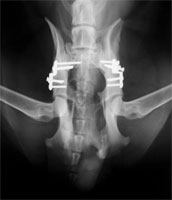

Es besteht keine Notwendigkeit von postoperativen Verbänden. Allerdings ist ein Belecken der Wunden ggf. durch Anlegen eines Halskragens zu verhindern. Unmittelbar postoperativ werden, solange sich der Patient noch in Anästhesie befindet, Kontroll-Röntgenaufnahmen angefertigt (Abb 12 und 13). Die deutliche Verbesserung der dorsalen Überdachung des Oberschenkelkopfes kann sofort gesehen werden. Die Lage des Implantates und der Schrauben werden kontrolliert.

DBO Röntgen präoperativ

Abbildung 12: Röntgen - präoperativ

DBO Röntgen postoperativ

Abbildung 13: Postoperative Röntgenkontrolle

Sechs Wochen postoperativ wird der Hund erneut einer Lahmheitsuntersuchung unterzogen und das Fortschreiten der knöchernen Fusion durch eine Röntgenuntersuchung in tiefer Sedation beurteilt. Gegebenenfalls wird zu diesem Zeitpunkt die zweite Seite operiert (Abb 15). Es zeigt sich in der Regel eine deutliche Kallusbildung an der Osteotomiestelle des Os ilium. Die Manipulation der Articulatio coxae sollte einen guten Grad von Beweglichkeit ergeben. In den besonderen Fällen, bei denen eine 40°-Platte eingesetzt wurde, kann die Abduktion und Extension des Hüftgelenkes ein wenig eingeschränkt sein. Ab Woche 6 sollte mit einem aktiven aufbauenden Bewegungstraining begonnen werden. Auf den besonderen Wert eine Physiotherapie braucht nicht hingewiesen zu werden.

DBO Kontrollröntgen nach 6 Monaten

Abbildung 15: Kontrolle nach 6 Wochen zeigt die Fusion des Os ilium auf der linken Bildseite. Die zweite Seite ist frisch umgestellt.